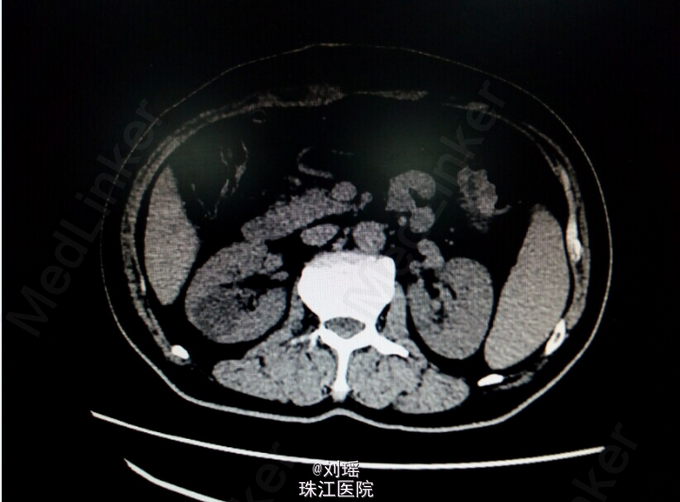

查体:生命体征平稳,慢性病容,皮肤巩膜重度黄染,右上腹T管,余无特殊。 辅助检查: 肝胆脾CT:右肾囊肿;胆总管粘液腺癌术后。 T管造影:胆总管全段可见不同程度,不同大小之充盈缺损并不同程度狭窄,考虑为占位性病变。肝内胆管明显扩张。